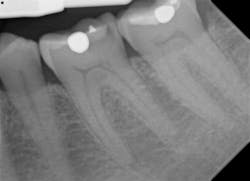

The resolution of DentiMax Open sensors provides 14-16 lp/mm actual, 25 line lp/mm theoretical on size 0 sensor and >20 lp/mm actual, 25 line lp/mm theoretical on the size 1, 1.5, and 2 sensors. Further, Dr. Gordon J. Christensen’s Clinicians Report says that “DentiMax’s sensors exhibited excellent resolution, sensitivity, image quality, and exposure latitude in controlled comparisons with other leading sensor brands.” Quality images are the result with bitewings (figure 9), anterior periapicals (figures 10 and 11), and posterior periapicals (figure 12).